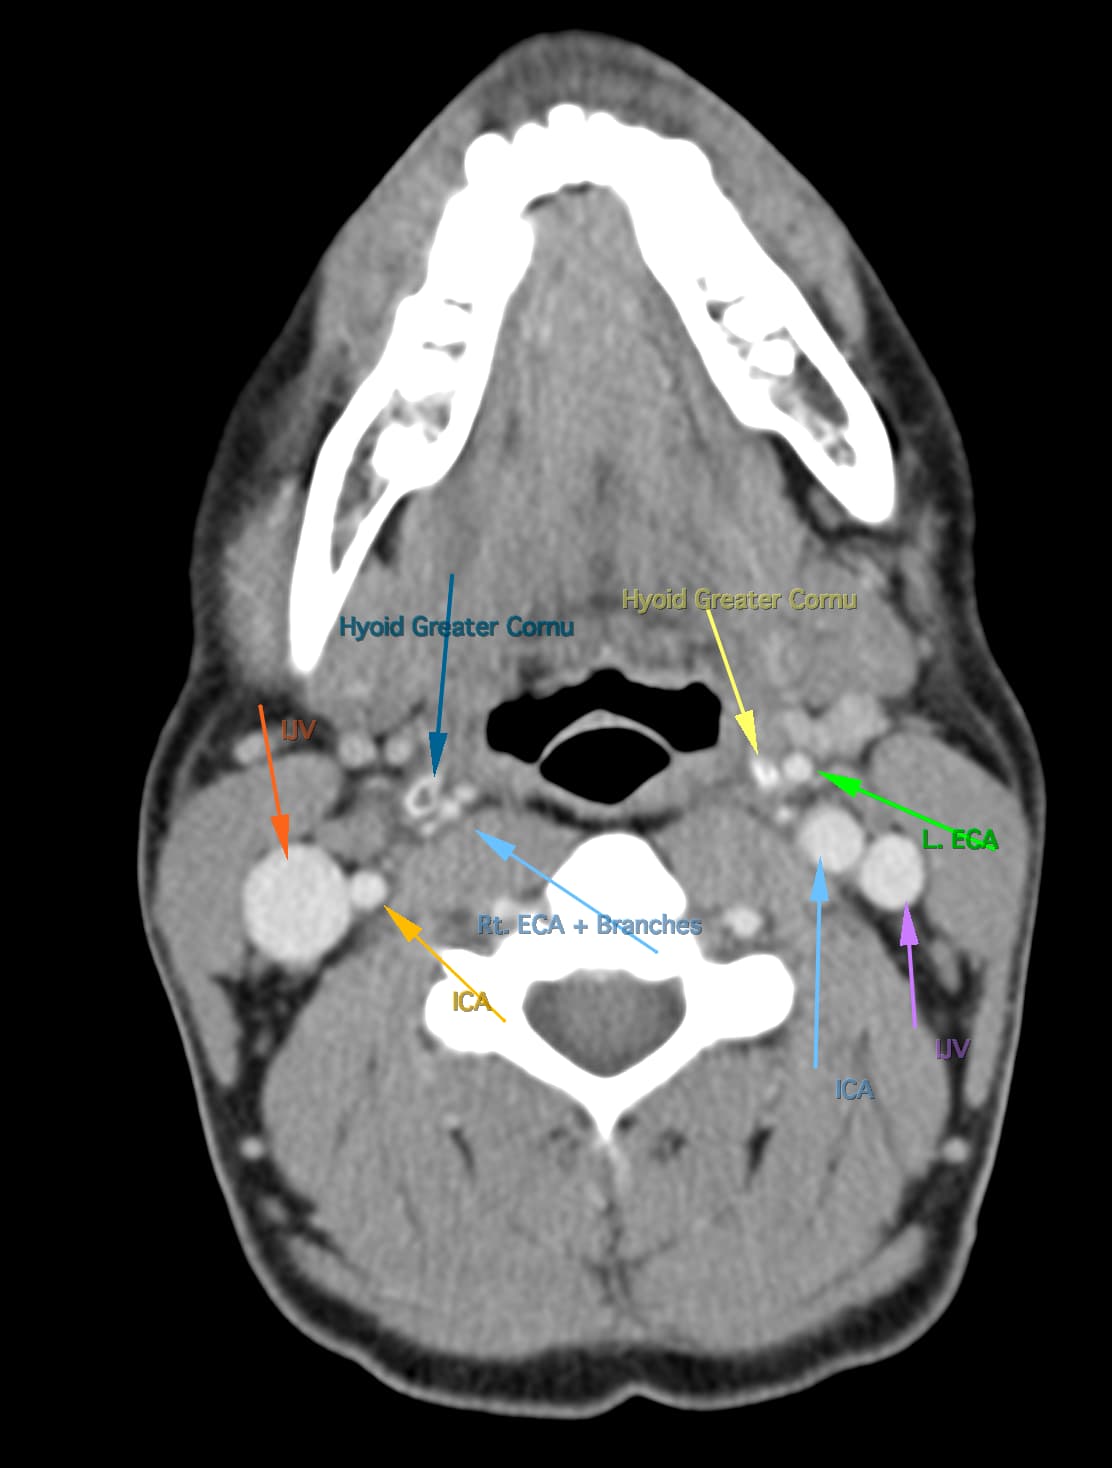

So, 2 years ago was the first time I came across Living with Eagle, filled with descriptions of all my symptoms, and a slew of scans showing very obvious bone chunks in the neck. Since I studied bio in college, and these bones are obvious, I figured I’d take a stab at looking at my own past scans and, low and behold, mild–but present–ossification of my stylohyoid ligament. Perhaps more relevant in my case, in the process of learning enough of the anatomy to understand axial images I noticed another weird thing–my right external carotid artery is in the wrong place. Instead of sitting lateral to my hyoid greater cornu, it’s medial. Hmm.

Tonsil surgery did solve the problem of my tonsils hurting, because they were gone, but no resolution of other symptoms. This was a year ago. I’ve been to PT, SLP, and now back to PT while I trial gabapentin for the neurologist. PT#2 discovered a bunch of significant atrophy in my upper right shoulder/back, and, you guessed it it’s all right sided. I’ve since then, thanks to radiopedia and Netter’s, also explored my images and noticed a few other anomalies in my scans, including an extended right thyroid superior cornu which appears to be pressing strongly into my neck also in the general area of pain, and an occipital artery branching off and wrapping around the internal carotid. Frustratingly these also weren’t mentioned on rads reports. My swallow study by the SLP showed obvious asymmetry with my swallow, but the SLP reported it symmetric and radiology apparently doesnt read the A/P view in their modified barium swallow studies? This is not inspiring faith in the academic institution I attended, but what can I possibly know they dont?